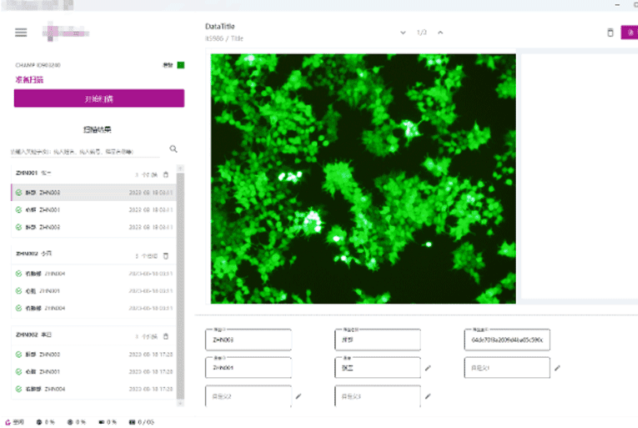

病理分析

血液分析

构建满足业务的图像处理分析软件

根据客户提供的专业知识或算法包,为客户构建满足行业需求的图像识别处理分析平台